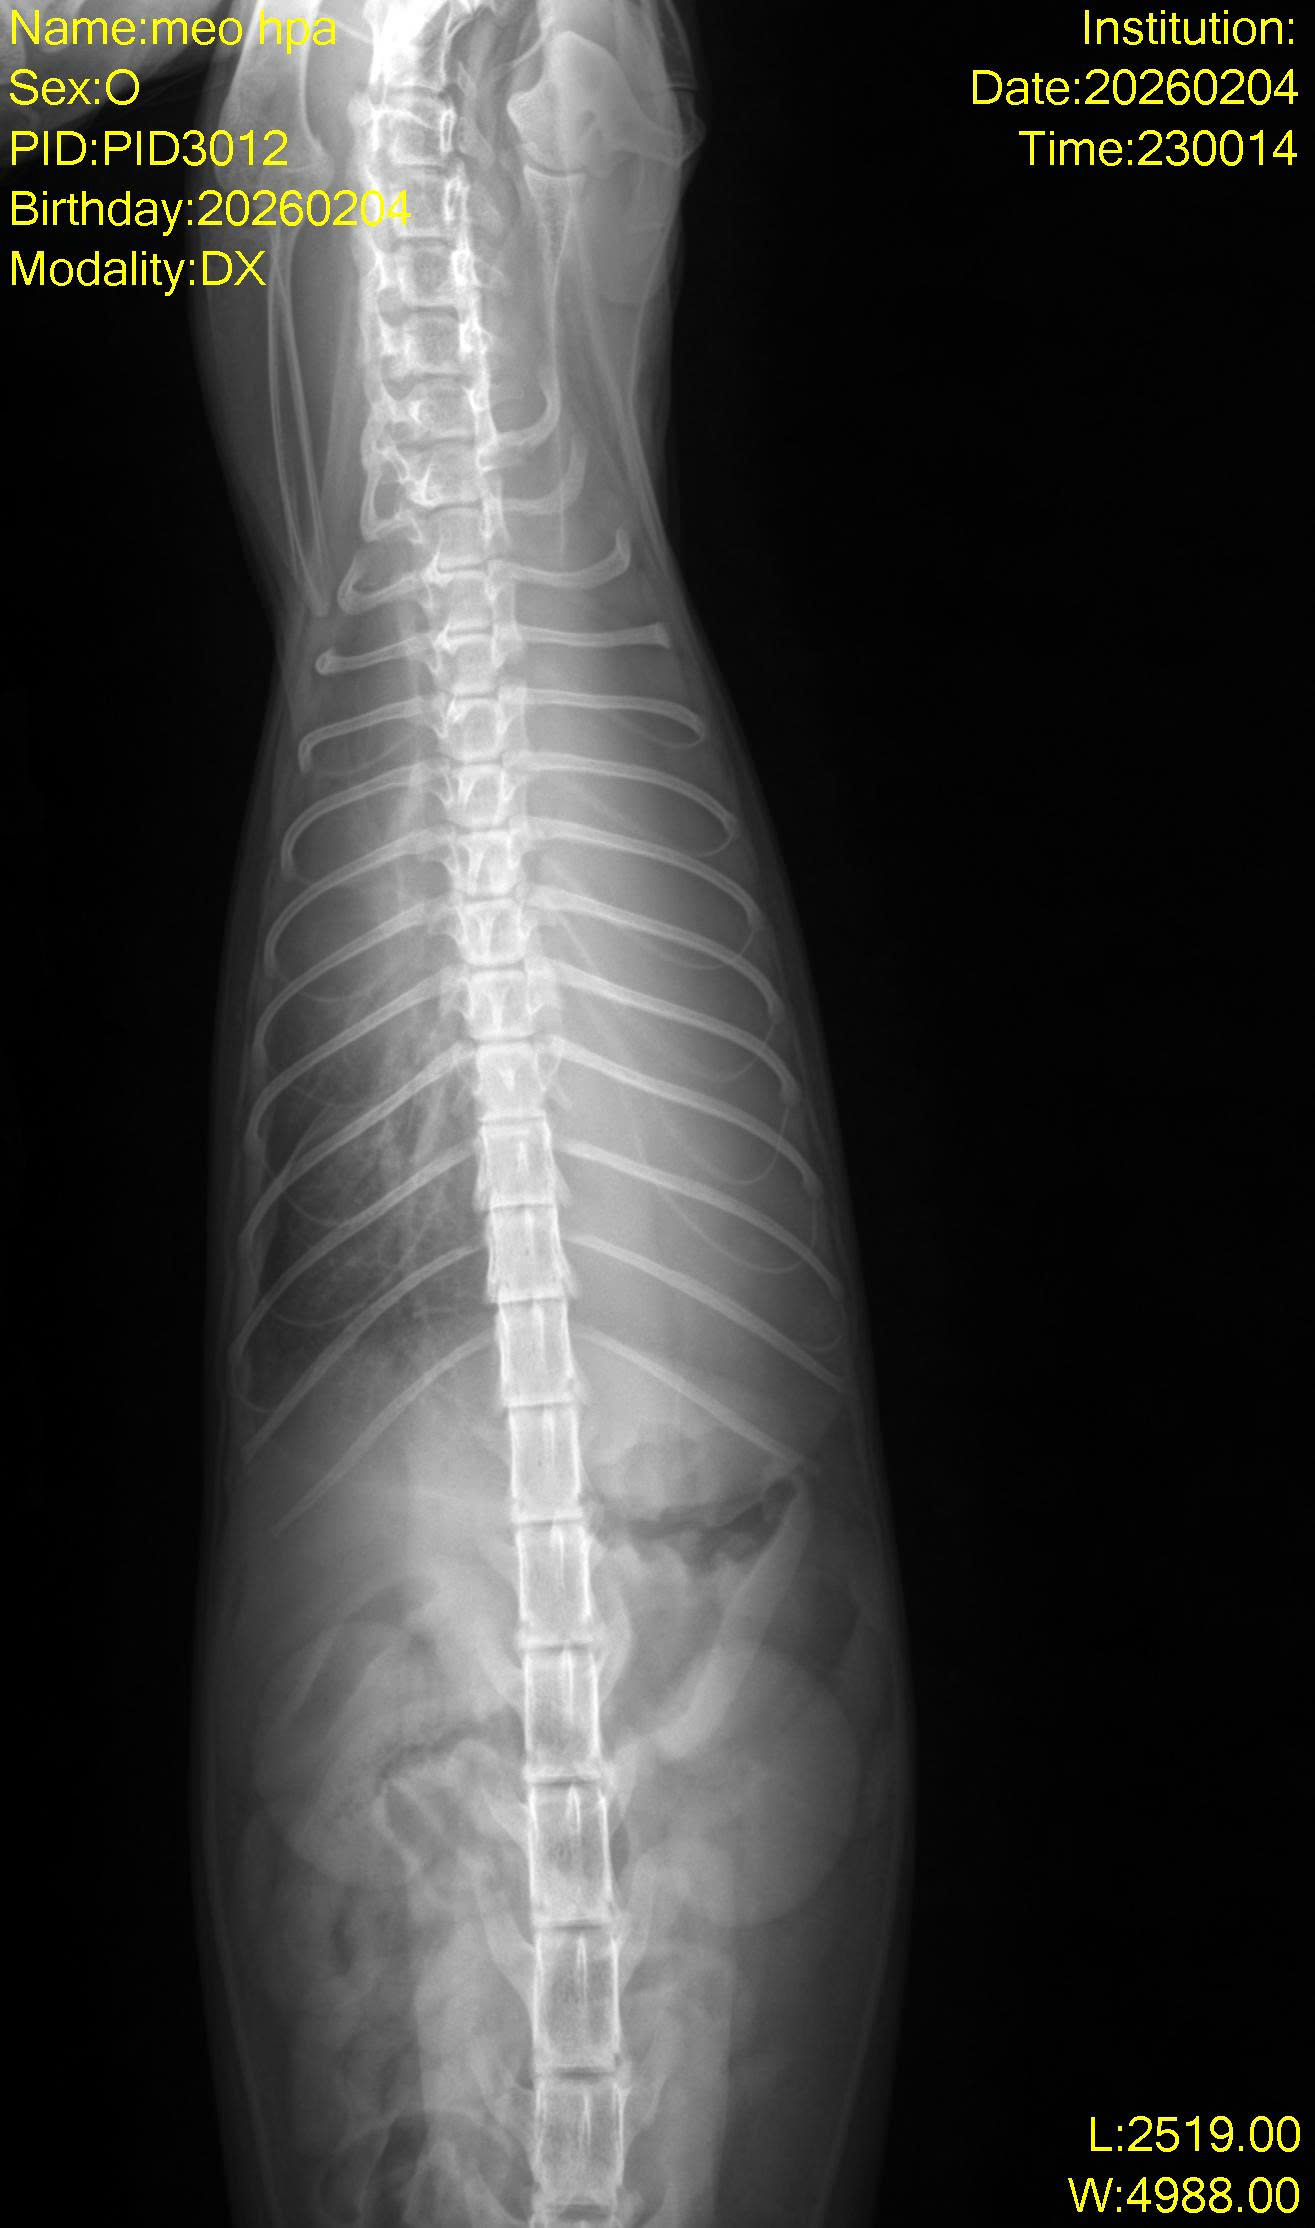

Bé được 1 bạn nhặt được ngoài đường. Bị khó thở, yếu. Đưa đến Solpet, chụp x-quang thấy tràn dịch màng phổi.